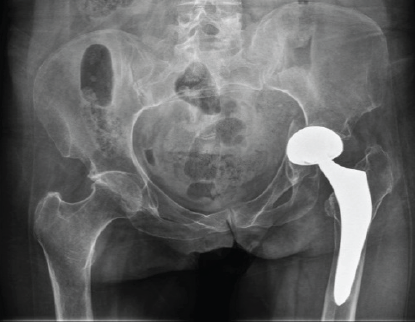

Radiographic evaluation, including computed tomography, revealed the protrusion of the acetabular cup into the pelvis, associated with a transverse acetabular fracture and a Vancouver AG-type fracture (Figs. 1 and 2).

Figure 1: Pre-operative pelvis antero-posterior X-ray.